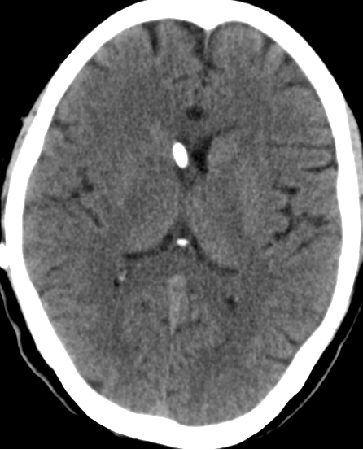

2014-10-17 CT

仍时有前额部疼痛,程度轻,调压190—200